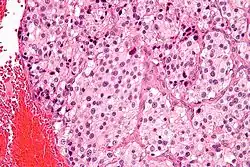

| Micrograph of a carotid body tumor (a type of paraganglioma) | |

The paragangliomas appear grossly as sharply circumscribed polypoid masses and they have a firm to rubbery consistency. They are highly vascular tumors and may have a deep red color.

On microscopic inspection, the tumor cells are readily recognized. Individual tumor cells are polygonal to oval and are arranged in distinctive cell balls, called Zellballen.[9] These cell balls are separated by fibrovascular stroma and surrounded by sustentacular cells.

By light microscopy, the differential diagnosis includes related neuroendocrine tumors, such as carcinoid tumor, neuroendocrine carcinoma, and medullary carcinoma of the thyroid.

With immunohistochemistry, the chief cells located in the cell balls are positive for chromogranin, synaptophysin, neuron specific enolase, serotonin, neurofilament and Neural cell adhesion molecule; they are S-100 protein negative. The sustentacular cells are S-100 positive and focally positive for glial fibrillary acidic protein. By histochemistry, the paraganglioma cells are argyrophilic, periodic acid Schiff negative, mucicarmine negative, and argentaffin negative.

Micrograph of a carotid body tumor Micrograph of a carotid body tumor